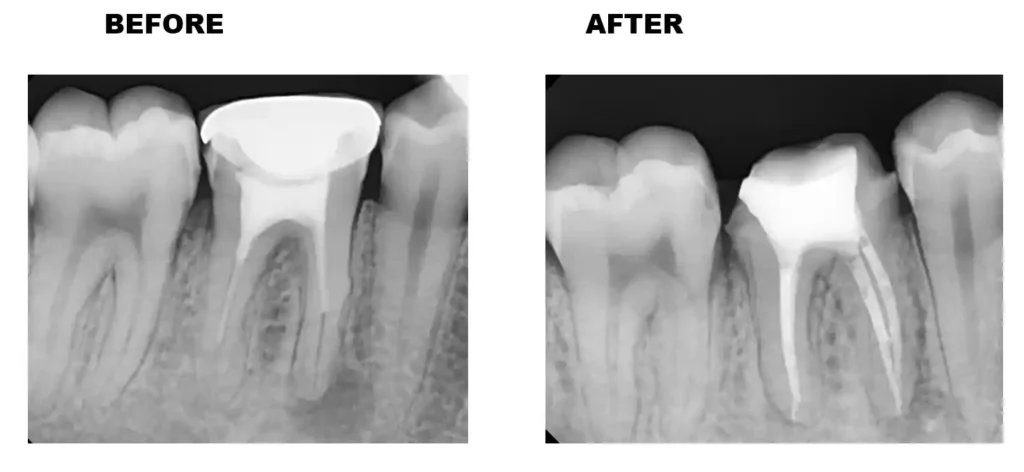

At Savani Dental, we use modern tools like digital X-rays and rotary endodontics to make the process faster, cleaner, and more comfortable than ever.

• Infected tissue is carefully removed and the root canals are cleaned and shaped

• The canals are filled under a rubber dam with a biocompatible material to seal them.

• A crown is placed to restore strength and appearance